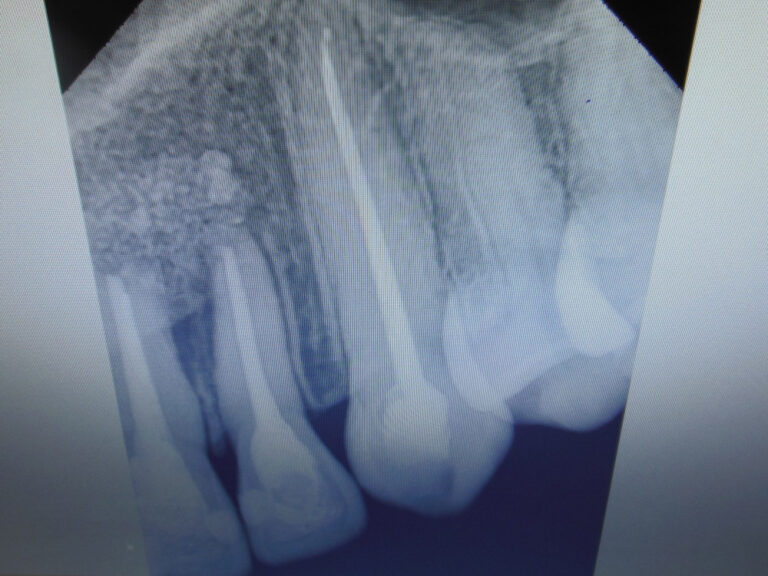

Ortodoncja CBCT

Leczenie chirurgiczno-ortodontyczne wad zębowych z zastosowaniem tomografii spiralnej CBCT w naszej klinice.